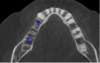

Co-diagnostic software was also used. While this type of software is available to practitioners from multiple manufacturers, in this case the laboratory provided the software. Co-diagnostic software allows for a prosthetically driven implant placement. In other words, the restorative outcome is taken into account prior to planning the placement of the implant. The software enables the team to incorporate the scanned image of the arch and the CBCT data to plan the surgery and fabricate a surgical stent, if so desired.12

This software allows accurate visualization of anatomic structures that are to be avoided during placement. This was especially important in this case because of the close proximity of the inferior alveolar nerve to the proposed implant sites. This planning has been found to lead to optimal results and allows the surgeon to place implants safely and efficiently.13-15

Once the scan and CBCT were loaded into the software, the respective files were merged to create a new image (Figure 2 through Figure 5). The data was then analyzed. The available software has vast libraries, some with up to 3,000 implant components from which to choose, from various manufacturers.12 The appropriate anterior-posterior position was determined, followed by the proper diameter and length of the implant bodies. This was all determined with the restoration in mind. The data was then used to fabricate a guide for the surgeon to use (Figure 6). These decisions were all made collectively by the team.